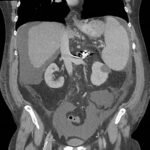

Endovascular coil embolization continues to become a more frequent modality of addressing hemorrhage and bleeding in patients. Migration refers to the coil unraveling or moving from the original embolization site. Migration of a coil is a known complication which can lead to serious consequences based on where the coil migrates. Despite increasing efforts to improve safety and technique, the risk of migration remains. We present a case of an embolization coil that migrated to the right ventricle, which was incidentally found roughly 2 months after undergoing an interventional radiology procedure for gastric variceal bleeding. The patient presented to the emergency department with dyspnea and abdominal pain. Unique images were obtained during his visit and in subsequent follow-up. As use of vascular embolization coils continues to become more commonplace, understanding the risks and complications of these procedures remains an important aspect of providing care for patients once they have left the interventional radiology suite. Coil migration should be a differential to consider in patients who present to the emergency department with signs or symptoms of arrhythmia or pulmonary embolism who have undergone a coil embolization procedure.